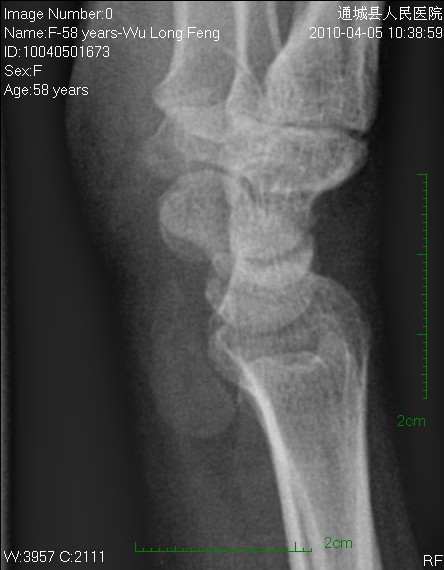

女性58岁,右腕肿痛就诊。平时右腕间断性疼痛,近来加重。

平片见桡前软组织内一密度增高、边缘光整块影

片后查体见右腕、掌轻度肿胀,腕腹侧按压无硬块,自己除有上述征状及类似手癣(痒、小水泡、死皮)外,关节活动无功能障碍。

片含诸构成骨无明显骨质破坏,软组织稍肿胀。片示软组织内异常密度影个人考虑为纤维组织增生,伴局部皮肤呈癣样变。考虑:银屑病性关节炎。建议作进一步检查。

1、腱鞘囊肿;2、舟状骨骨折,是否有可能是创伤后软组织遗留下的某种改变。

我考虑腱鞘囊肿可能性大。另尺骨稍长,月骨、三角骨尺骨关节面密度减低。考虑尺骨撞击综合症

这个位置这么大的东西竟然摸不到块,应该不是软组织内的吧。